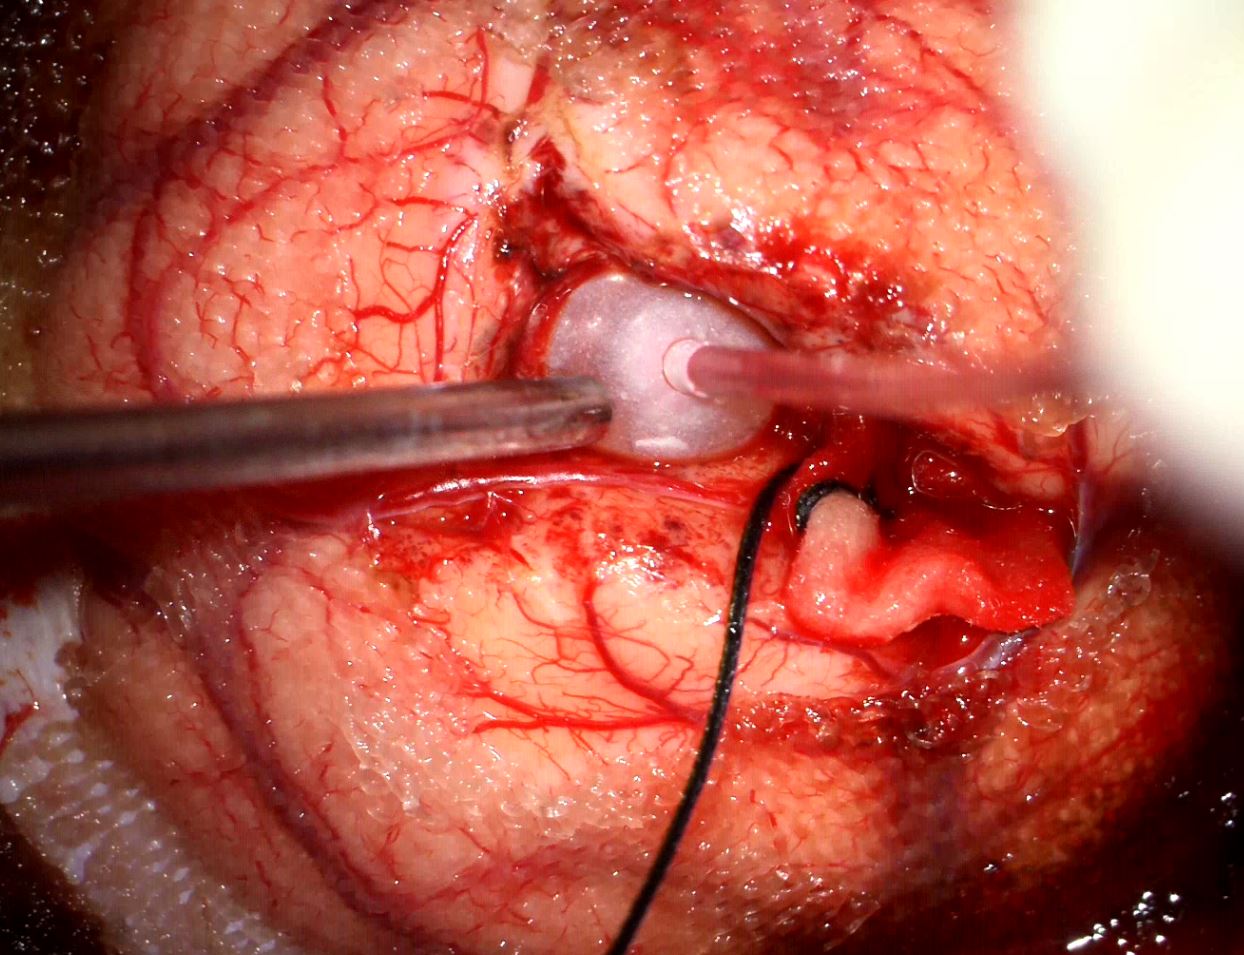

Διενεργήθη διαφλοιική προσπέλαση με τη βοήθεια νευροπλοήγησης και ολική (Simpson I) εξαίρεση της βλάβης.

Στη συγκεκριμένη περίπτωση, με τη βοήθεια του νευροπλοηγού και της μαγνητικής δεσμιδογραφίας επιλέξαμε μια οδό η οποία ήταν σύντομη , αποφεύγοντας ταυτόχρονα κρίσιμα νευρικά δεμάτια. Χρησιμοποιώντας ελάχιστα επεμβατικές τεχνικές ελαχιστοποιήσαμε το τραύμα στον εγκέφαλο (βλ. Διεγχ. Εικόνα η οποία δείχνει την τεχνική της διήνησης με μπαλονάκι – balloon dissection).